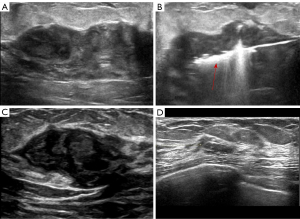

Before the procedure, ultrasound was used to determine the size, extent, echogenicity, shape, and boundary of the lesions, and color Doppler flow imaging was employed to assess blood flow and distribution when necessary. Based on these findings, the sonographer and surgeon jointly developed an individualized ablation plan, determining the puncture site, needle depth, ablation range, number of puncture treatments, and treatment dose. Patients were positioned supine, with routine disinfection and draping. Under ultrasound guidance, the MWA needle was inserted into the lesion, and the ablation power and time were set at 30 W (Figure 1). For smaller lesions, a single or multipoint ablation strategy was used, whereas for larger lesions, a mobile ablation strategy was employed. The ablation range encompassed the entire lesion and extended beyond its margins by at least 5 mm. Glucose-water isolation technology was utilized to protect adjacent structures such as the skin, areola, and retro-mammary space.

Patients were followed up every 3 months with physical examination and ultrasound examination until 24 months post-treatment (Figure 2).